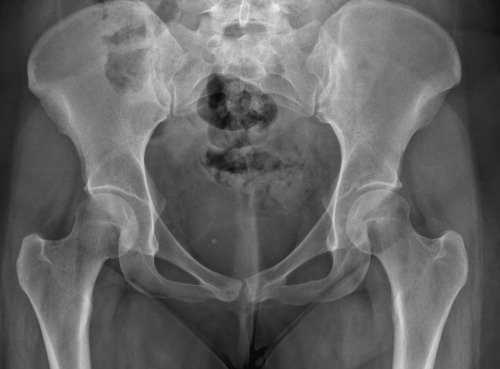

Não sei por onde começar porque e uma história longa e vou tentar resumir, fiquei meses tentando descobrir que eu tinha fibromialgia, porém eu não tenho só isso, tive edemas na coluna, problemas na lombar, e até derrame pleural eu tive, eu pago aluguel que e 1300 mais o condominio que e 450, fora que eu me planejei e não tenho familia pra apoiar entre outras coisas, quando me mudei e planejei pra poder ter o proprio ape eu não sabia que do nada iria ficar doente, em março de 2023 eu pego as chaves mas até la ta dificil, fiz emprestimo e várias outras coisas porque só a medicação de durogesic que eu uso e restiva um a caixa e 650 e o outro 300, podem pesquisar, após um procedimento na lombar cirurgico pra tentar aliviar a dor descobri uma necrose asseptica na cabeça dos dois femur, com risco de ter que colocar uma protese, até pouco tempo estava de muleta, só podia ficar sentada, e mesmo a dor e muito forte, eu ainda não sei a tal outra doença que eu tenho, já aconteceu de eu entrar na emergência e ficar na UTI, tive mais de 10 internações no hospital e não e mentira, minha maior luta e conseguir tratar essa necrose, poder voltar a praticar esportes, sei que tem gente que precisa muito mais mas eu cheguei no meu limite e to até com um aluguel atrasado, todas as coisas que eu estiver pagando eu vou colocar nota fiscal porque eu não to aqui pra fazer ninguém de trouxa, vou colocar exame, fotos de internação entre outras coisas que posso, porque tem algumas que não posso devido porque não quero imagem negativa para local de trabalho (e aonde eu trabalho eles estão me ajudando e muito), e de acordo de como for funcionando a vakinha eu vou vendo se aumento, eu só queria me livrar dessas contas sufocantes primeiro, e agora os médicos estão lutando pra descobrir a outra doença que tenho além dessa da necrose que ta me deixando muito mal e que a fibromialgia atrapalha a descobrir, sei que e chato porque já pedi ajuda 2 vezes, mas conversei com amigos e infelizmente eu não tenho outra opção a não ser pedir ajuda, vou colocar exame de tudo etc, o valor até de emprestimos que estou devendo e tudo mais, e podem me perguntar qualquer coisa que eu respondo e claro, vou postar nota fiscal pra provar que to pagando o que to mostrando, eu to no meu limite, e não e fácil, eu ficava 3 dias seguidos sem conseguir dormir e os médicos não conseguiam descobrir e ainda sigo firme no tratamento porque vou encontrar uma resposta e não posso desistir do tratamento, eu poderia fazer um textao aqui mas com poucas palavras já consigo ser direta, obrigada a quem ajuda e continua me apoiando desde o começo e pra quem não gosta e não acredita e só não ajudar, ninguém vai ficar inventando internações etc pra ficar ai pedindo dinheiro de graça pra ostentar, não gosta só não infernizar, só cada um sabe o sofrimento que ta passando na própria pele e a sua luta diária, agradeço se puder ajudar, aceito tudo que seja positivo e desejo o dobro de bom pra cada um.